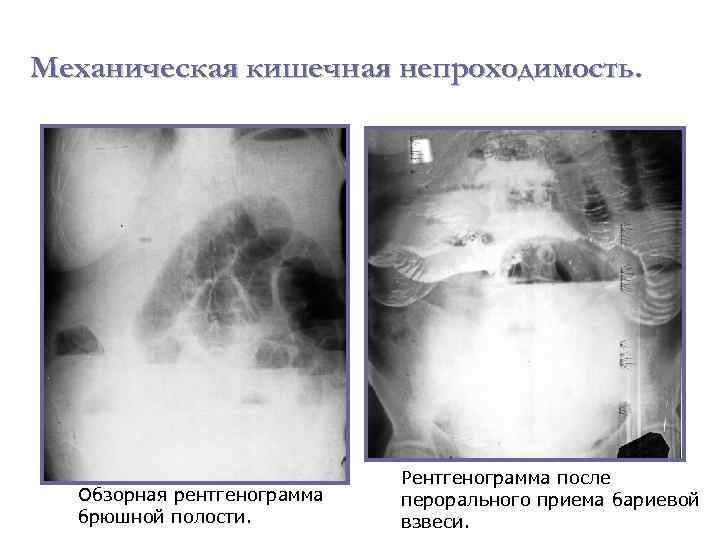

Иллюстрации и информация о симптомах острого кишечного непроходимости